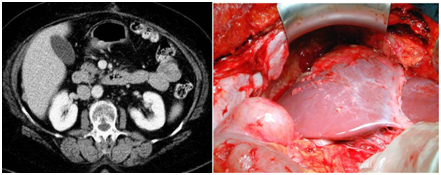

Figure 2 CT image of solid oval implant of homogenous structure, 27х16mm in Douglas space.

Figure 3 Confluent implant of greater omentum on CT scan and intraoperative image.